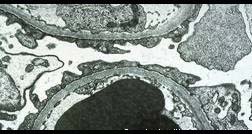

- 单项选择题肾病理光镜及免疫荧光正常,观察电镜下改变, 其病理诊断 ( )

E、微小病变